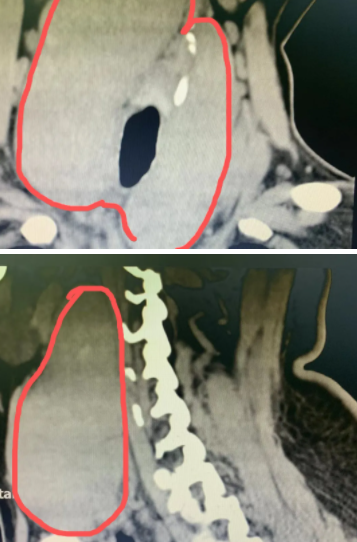

一查吓一跳,张姐脖子两侧的甲状腺已经肿大到近 12 cm,而且能明显感到,在这两个大「腰子」压迫下,张姐呼吸急促。

肉眼看起来张姐只是脖子粗大,突出并不明显,但「魔鬼」都藏在里面,点击下图,可看到取出的两个巨大甲状腺肿。

对于张姐而言,无论是哪一种,肿大到 12 cm 的甲状腺已经向上延伸到了下颌骨,向下钻进了胸骨后,手术刻不容缓。